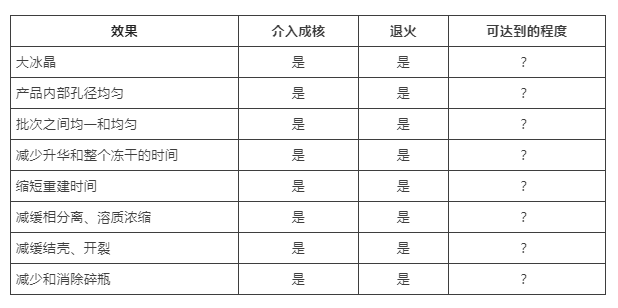

有没有发现,退火工艺的作用,和介入成核高度重合?区别是:退火只是一个特殊的工艺设置,虽然温度、持续时间也需要通过实验数据做更深入的研究;但对于客户来说,不需要增加额外投资;在冻干工艺这个领域,始终“技...